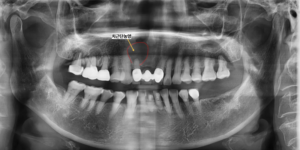

이번 동탄치과 환자는 70대 여성으로

앞니 잇몸이 심하게 부어 내원하였습니다.

검사 결과 앞니 치아 뿌리 부위에 발생한

치근단농양의 크기가 치아 크기보다

더 크게 관찰될 정도로 매우 심한 상태였습니다.